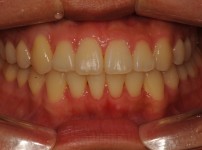

5

BEFORE

AFTER

클릭 해주세요.

전체치아교정

치아교정